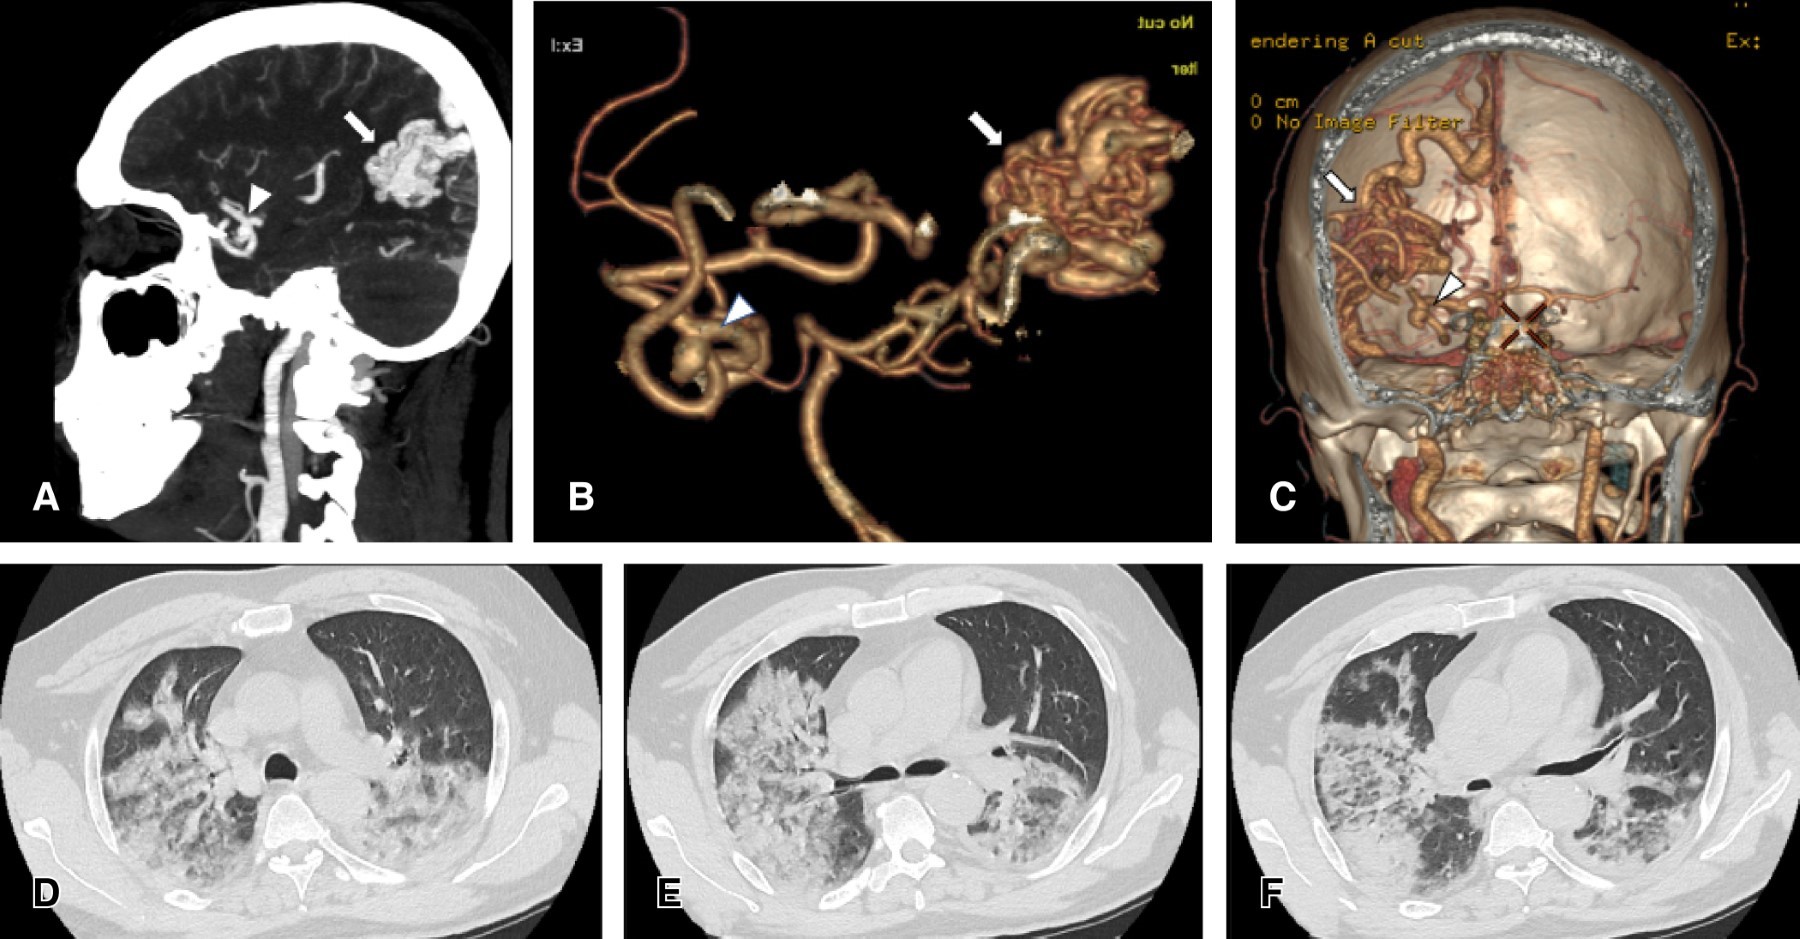

A partir del segundo día, en la emergencia aumentaron los síntomas y signos respiratorios, lo que ameritó iniciar oxigenoterapia. En el cuarto día de estancia en emergencia se realizó una angiotomografía cerebral, donde se identificó un aneurisma de la arteria cerebral media derecha de 5 mm de tamaño y una malformación arteriovenosa ipsilateral de 23 × 32 × 37 mm. Asimismo se realizó una tomografía pulmonar que evidenció un compromiso pulmonar promedio de ambos pulmones en 60% (Figura 2). Durante el séptimo día de estancia en emergencia, el paciente persistió con insuficiencia respiratoria grave, que no había respondido al manejo con máscara de presión positiva continua en las vías respiratorias (CPAP: Continuous Positive Airway Pressure), además presentó disminución de la ECG a 12 puntos e ingresó a la unidad de cuidados intensivos (UCI).

Figura 2